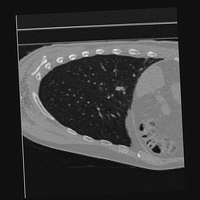

Exp. 3: Adult thorax data: To show the versatility of our approach we also apply it to adult thorax scans. For this experiment no organ specific training is performed but the whole volume is used. We evaluate reconstruction performance similar to Exp. 1 and prediction performance when is projected on an external plane, comparable to X-Ray examination using C-Arms. The latter provides insights about our method’s performance when applied to interventional settings in contrast to motion compensation problems. 60 healthy adult thorax scans were randomly selected, 51 scans used for and nine scans used for . Each scan is intensity normalised and resampled in a volume of with spacing . Using the Fibonacci sampling method, 25 sampling plane of size , evenly spaced between -50 and +50, were rotated over 500 normals. Training took approximately 20 hours for 60 epochs. Fig. 4c shows an example reconstruction result gaining 28dB PSNR with additional SVR. prediction takes approx. 20 ms/slice for this data.

0..5.3 Exp. 3:

We replicated the experiment on adult thorax data without specifically segmented organs. This approach was applied to CT acquisition, shown in Fig 13 and 14, as well as Digitally Reconstructed Radiographs generated using Siddon-Jacobs Ray Tracing shown in Fig. 16.